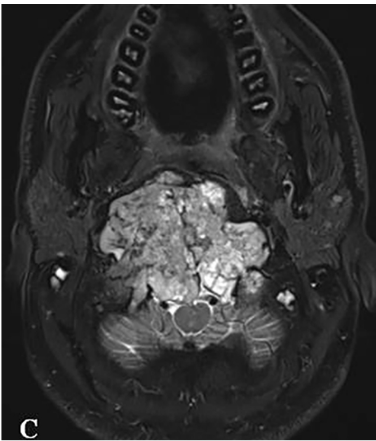

MRI和CT扫描显示巨大颅颈交界区脊索瘤,肿瘤最大直径达10cm、瘤体积96.5cm³,肿瘤并向双后外侧延伸浸润性生长,较多侵犯右侧,肿瘤延伸至椎前间隙、下斜坡、双侧枕骨髁、第一颈椎C1的前弓以及C2的齿状突,巨大肿瘤压迫脑干和双侧椎动脉移位,并向硬膜内压迫扩张。

▼术前MRI

▼C:术前MR显示肿瘤巨大延伸,并浸润长入硬膜内的脑实质。F:术后MR显示全切肿瘤和脑干延髓占位压迫得到解除。